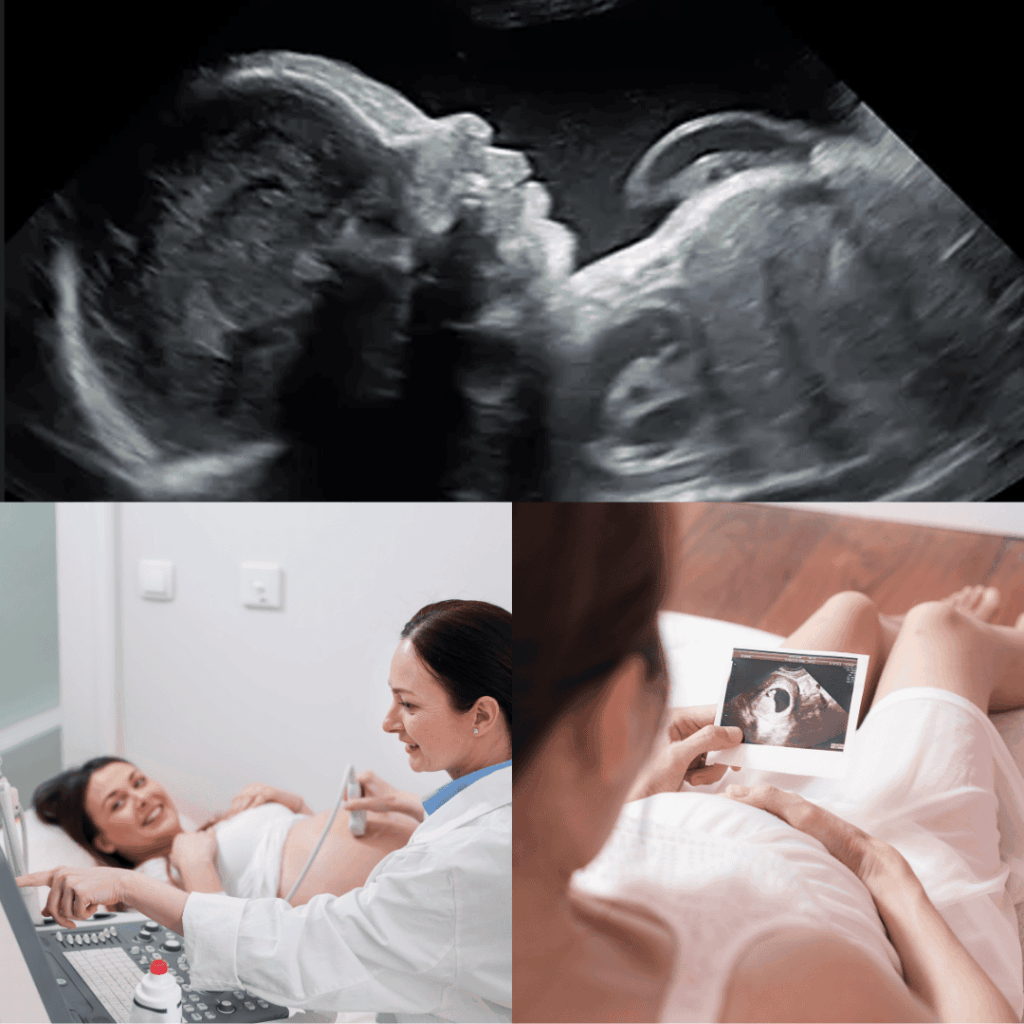

A maternity ultrasound scan uses gentle sound waves to create images of your baby during pregnancy. It offers parents the opportunity to see their baby, strengthen bonding, and capture meaningful moments throughout the pregnancy journey.

Scans may be performed at different stages of pregnancy, including early scans to visualise the pregnancy and later scans to observe your baby’s growth and movements. An anatomy screening provides a general visual review of your baby’s physical development based on standard screening views, offering reassurance and a memorable experience for expectant parents.

All maternity ultrasound scans are conducted by trained professionals sonographer and are intended for screening and observation purposes only.